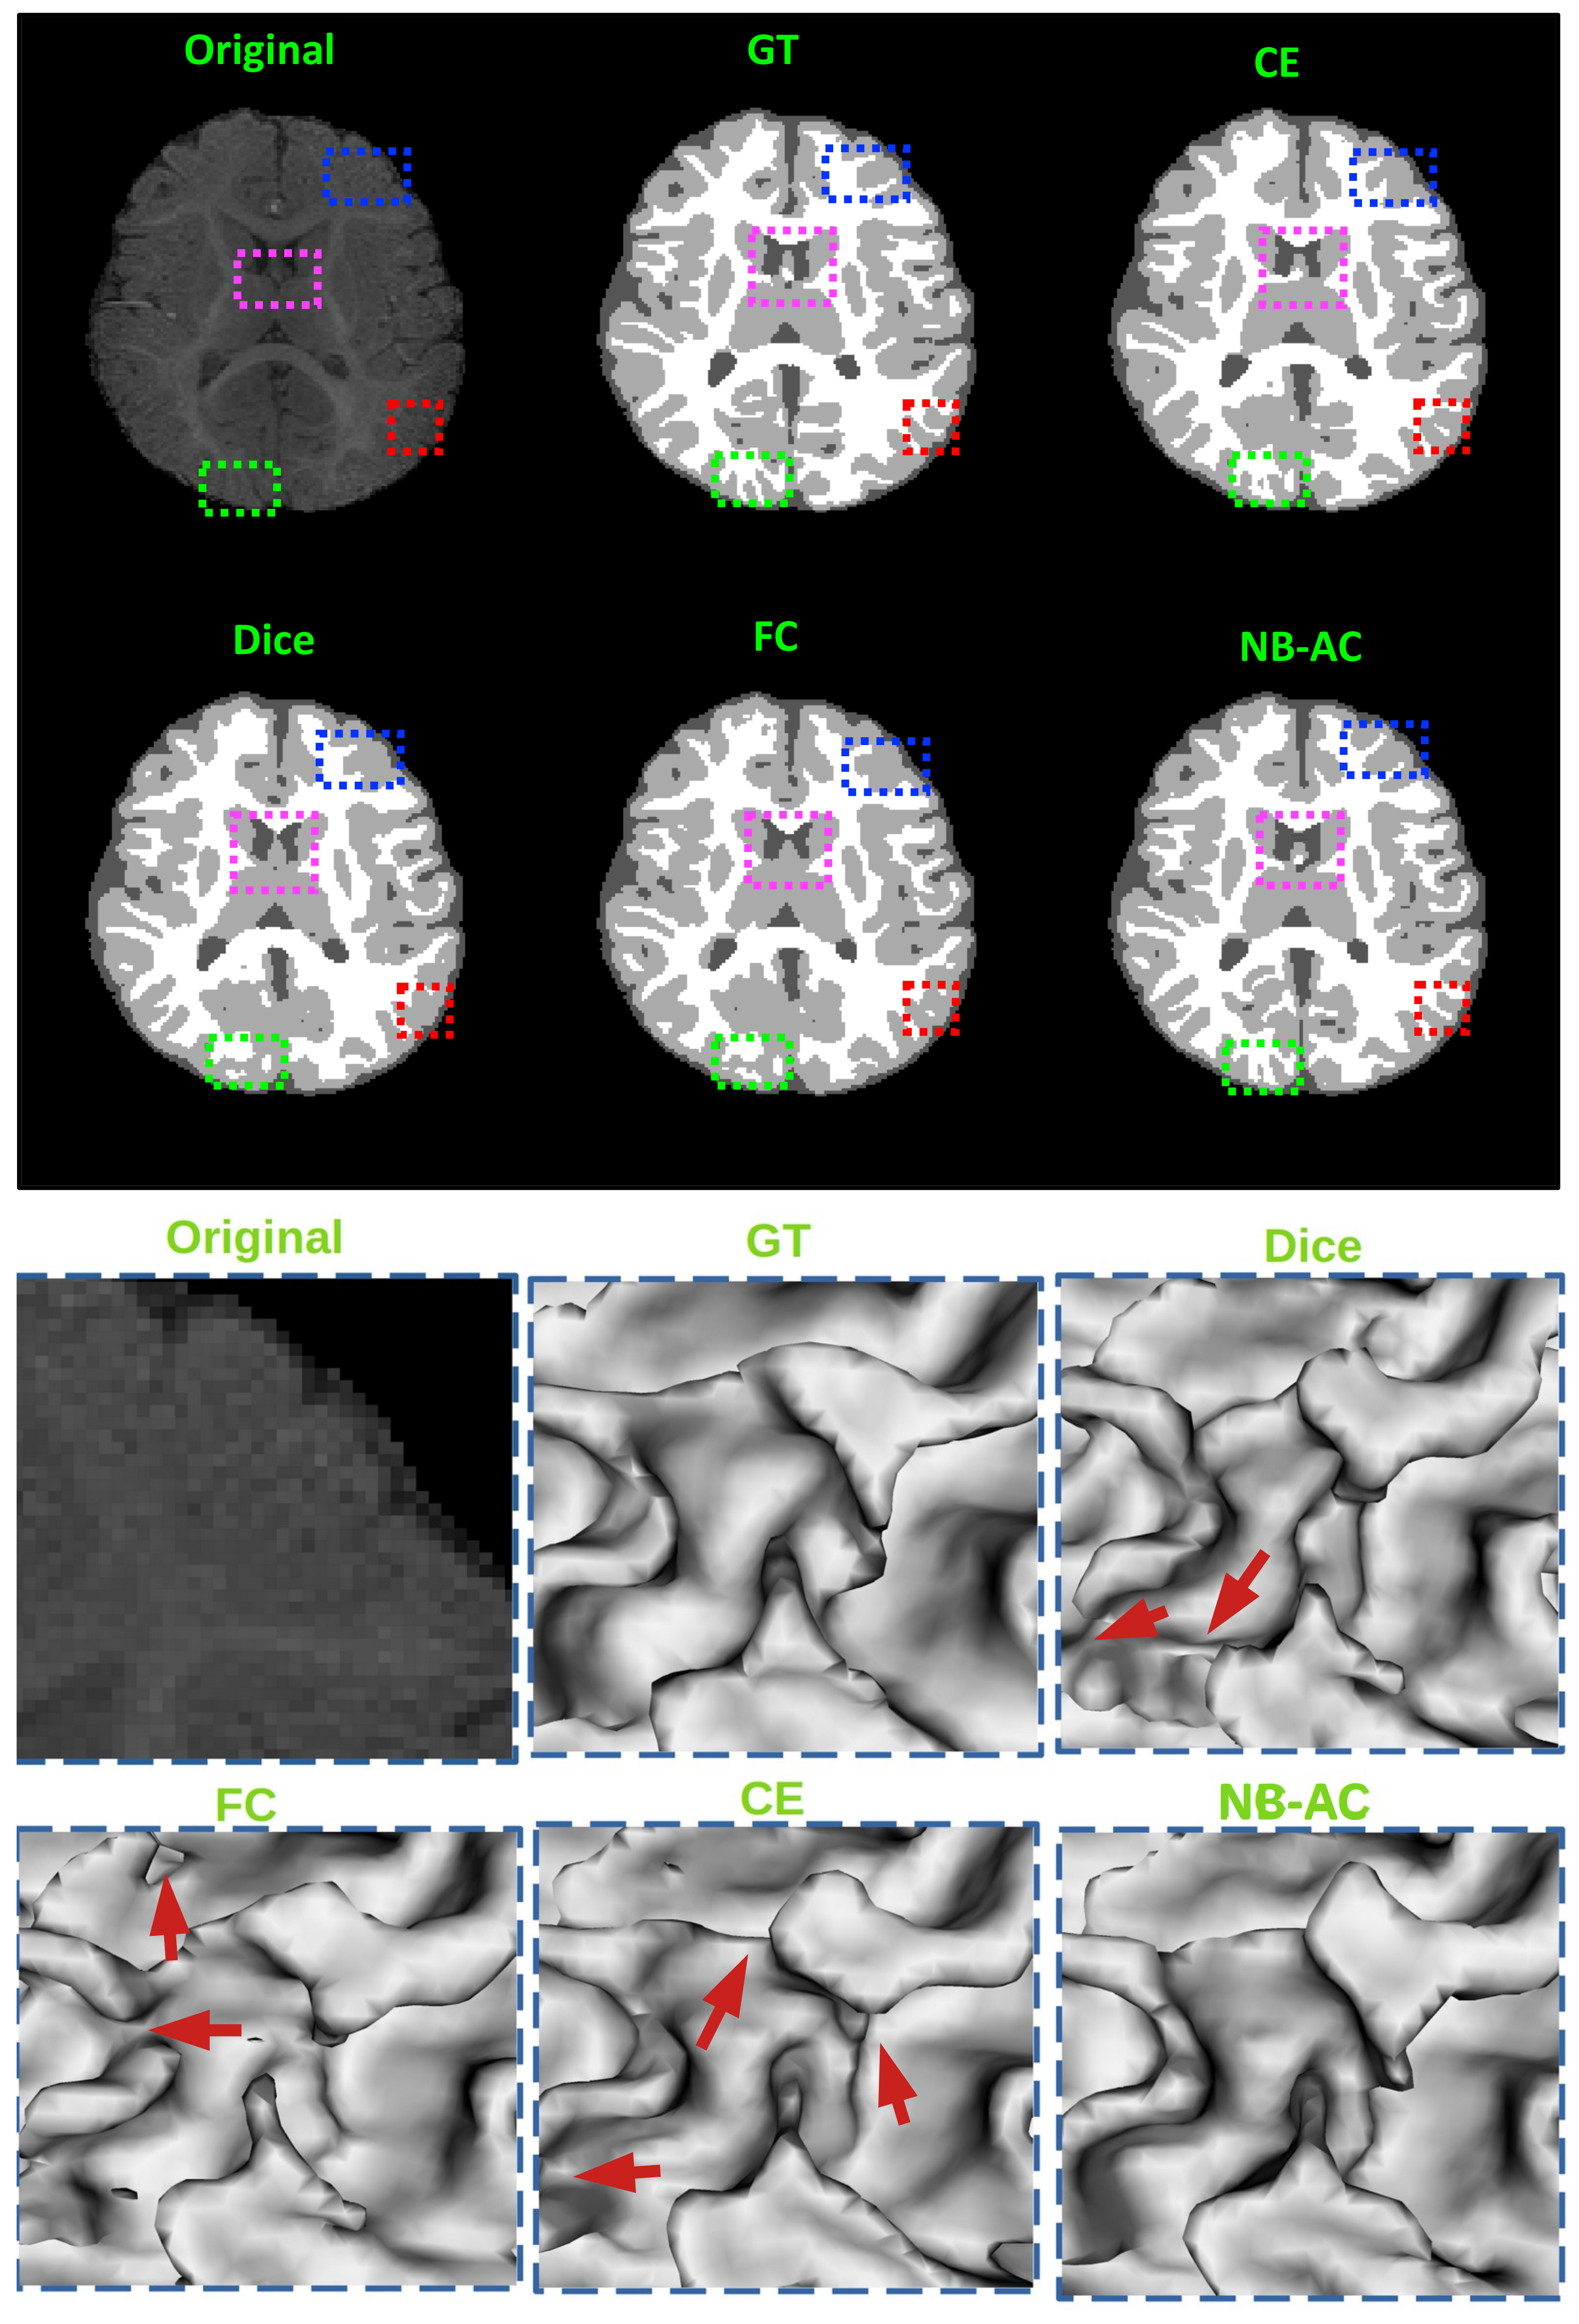

Figure 11.

top: Comparison of our proposed NB-AC loss against other loss functions on the iSeg17 dataset with colored boxes highlighting specific differences. bottom: A closer look is also given with the topological errors indicated by red arrows.

Figure 8, Figure 9, Figure 10 and Figure 11 visualize the comparison between our proposed NB-AC loss against other loss functions including Dice, Focal (FC) and Cross Entropy (CE) on the Unet framework. These images are randomly selected from the testing set of various datasets, namely DRIVE, MRBrainS 2018, BRATS 2018, iSeg 2017. As shown in Figure 1, medical images contain poor contrast images where the boundary between objects is very unclear and weak. Take the iSeg dataset as an example, due to the myelination and maturation process of the infant brain, the boundary between classes in the infant brain in iSeg is very weak, leading to difficulties for segmentation. The segmentation results from different loss functions are visualized in Figure 11(top) with specific differences highlighted in colored boxes. The infant brain MR images (iseg-2017 dataset) have extremely low tissue contrast between tissues; thus, the segmentation results using traditional loss functions (such as CE, Dice, and Focal loss) have large amounts of topological errors (contain large and complex handles or holes) in the segmentation results, such as the WM surface in the Figure 11(bottom) which illustrates an enlarged view of the white matter surface of an infant brain. Figure 11 (bottom) demonstrates that the proposed NB-AC loss function produces less topological errors (i.e., holes and handles), indicated by the red arrows, compared against the existing loss functions. In addition to the 2D view of the brain as in Figure 11, the 3D view of the entire white matter surface, as in Figure 12, demonstrates that the proposed NB-AC loss function produces less topological errors (i.e., holes and handles), indicated by the red arrows, compared against the existing loss functions.

The segmentation results from different loss functions are visualized in Figure 11(top) with specific differences highlighted in colored boxes. Figure 11(down) illustrates an enlarged view of the white matter surface of an infant brain from the regions highlighted in blue boxes of Figure 11(top). Figure 11(down) demonstrates that the proposed NB-AC loss function produces less topological errors (i.e., holes and handles), indicated by the red arrows, compared against the existing loss functions. For a more detailed visualization, we provide the entire view of the white matter surface obtained from different loss functions in Figure 12.